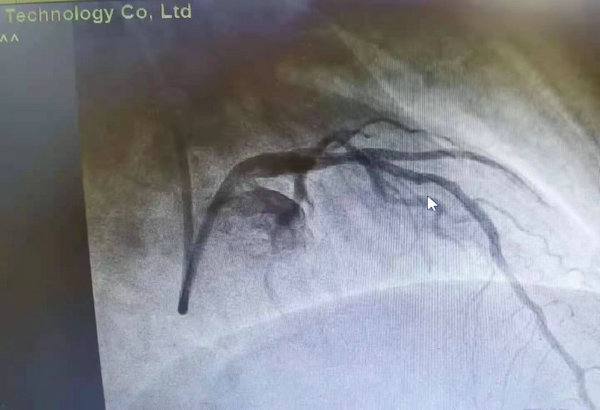

术后植入可吸收支架狭窄处消失

可吸收支架也称生物可降解支架、生物全降解支架,采用在人体内可降解吸收的材质制成,支架携带药物,通过药物缓释抵御血管再狭窄,最终降解并完全被组织吸收,血管结构功能恢复。经过与患者及家属的充分沟通和充分术前检查及评估后,决定为患者植入生物可吸收支架。手术过程十分顺利,术后无不良反应。